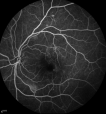

早期糖网-血管瘤样改变

中期糖网血管闭塞及新(xīn)生血管形成

晚期糖网